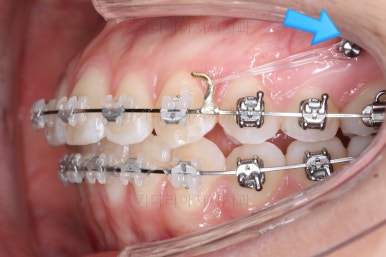

장치를 부착한 직후츼 사진입니다.

장치를 따라 걸려있는 철사의 형태를 보면 생각보다 많이 틀어져 있었구나 하고 느껴지게 되실거에요.

이번에 부착한 장치는 엠파워 클리어라고 하는 자가결찰 세라믹장치 입니다.(아마 이 장치 나올 때마다 설명드리는 것 같은데) 매우 유명한 클리피씨라고 하는 장치와 같은 컨셉의 장치입니다.

단지 제조 회사가 다를 뿐이죠.

(엠파워는 미국장치, 클리피씨는 일본장치)

술자의 선호도에 따라 장치가 선택되는데 클리피씨 보다는 부산치아교정잘하는곳인 키다리아저씨치과에서는 엠파워를 약간은 더 선호하고 있습니다.

추가로 사용한 장치는 바로 미니스크류(마이크로 임플란트) 장치입니다. 화살표를 보시면 잇몸뼈에다가 매우 작은 크기의 스크류를 식립해서 전체 치열을 밀고 당기고 해주는 거에요.